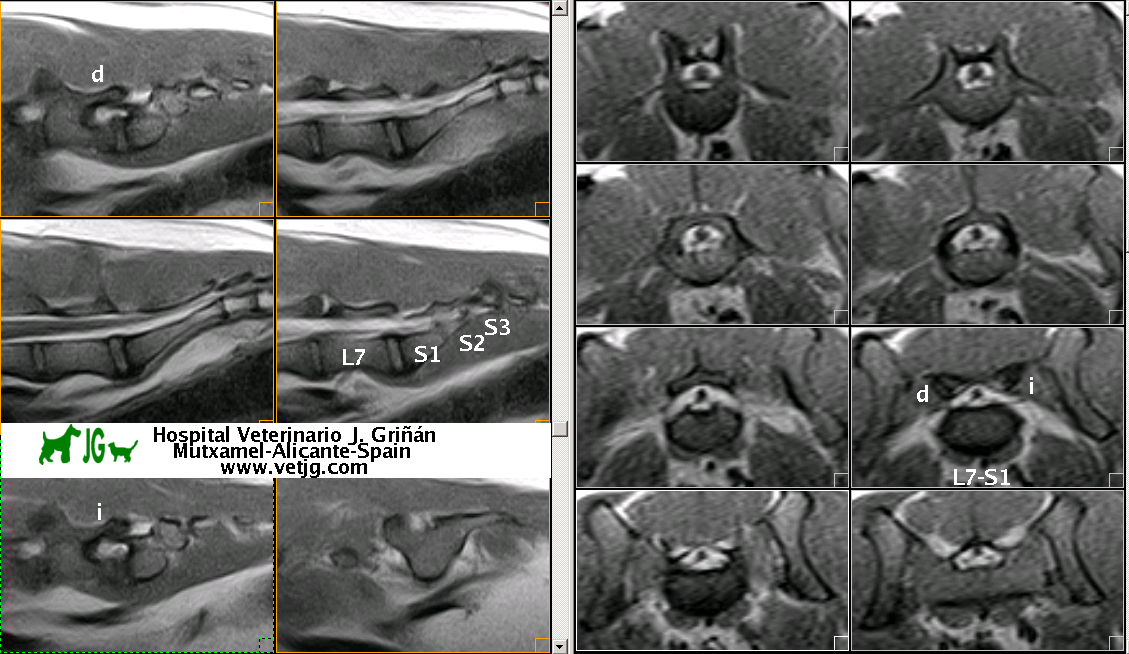

Articulación lumbosacra normal (perro labrador). Nótense las salidas radiculares, derecha (d) e izquierda (i) de la raíz L7-S1 |

La médula espinal acaba en L5, donde empieza la cola de caballo |

Resonancia magnética lumbo-sacra de pastor alemán |